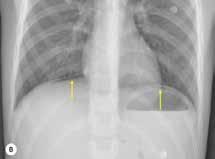

Se revisaron las pruebas solicitadas en Urgencias. En la analítica se en contró una hemoglobina (Hb) de 14 g/dl, un volumen corpuscular medio (VCM) elevado (106μ³) compatible con su historia de alcoholismo o con un déficit de ácido fólico o vitamina B12, una discreta elevación de la proteina C reactiva (13,2 mg/dl) sin elevación de otros reactantes de fase aguda y unas enzimas hepáticas dentro de la normalidad, con la aspartato transfe rasa ligeramente elevada 39 U/L (rango de normalidad: 5-34). Los tóxicos en orina fueron negativos, así como la etanolemia. La radiografía (rx) de tórax mostraba una condensación en el lóbulo superior izquierdo en posi ble relación con la infección tuberculosa diagnosticada en 2011 (Figura 1). La TC -a pesar de no mostrar signos de patología aguda intracraneal, ni masas ni signos de sangrado- sí que mostraba atrofia cerebral con surcos muy marcados, hallazgo no concordante con la edad de nuestro paciente (Imagen 2).

Figura 1. Radiografía de tórax en bipedestación AP y Lat.

Lesiones residuales/cicatriciales en campo superior izquierda, con aumento de densidad de parénquima, bronquictasias y pérdida de volumen, en relación con antecedente de TBC. Parénquima pulmonar derecho aceptablemente ventilado. Siluesta cardiovascular normal.